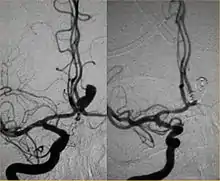

Parallel to the development of catheters, in the radiology and neuroradiology units, image technology dramatically improved: Charles Mistretta in 1979 invented digital subtraction angiography (DSA), the technique currently in use. It consists of performing skull radiography under basic conditions which are then "subtracted" to the image after contrast media injection, to provide an image where only brain vessels are displayed, with great improvement in the diagnostic potential.

Between the end of the '80s and the beginning of the '90s, INR was suddenly revolutionized after the work of two Italian physicians: Cesare Gianturco and Guido Guglielmi. The first combined a deep knowledge of diagnostic radiology with a great ability to solve technical and manual problems. He invented Gianturco's coils, which he used to make the first attempts to embolize arteries and aneurysms.[8] Gianturco also patented the first endovascular stent approved by the American FDA;[8] a device with a great legacy. In the second half of the 1980s, Sadek Hilal was the first in Columbia University to use coils to treat brain aneurysms; but this technique was inaccurate and dangerous because the coils were released with little control with great risk of occluding the vessel from which the aneurysm originated (parent vessel).[9] The coil embolization was revolutionized by the work of Guido Guglielmi in UCLA, who realized that electricity could function as a controlled release mechanism for coils; in 1991 he published two works dealing with the embolization of brain aneurysms by means of detachable platinum coils[10] (Guglielmi's coils). The treatment of aneurysms was thus made more accessible and safe.